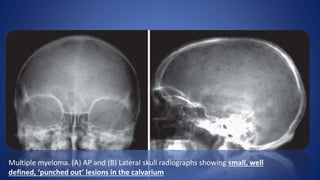

• CLASSICAL APPEARANCE - Well defined, osteolytic , punched

out lesions throughout the skeleton, most characteristic in the

skull .

Multiple myeloma. (A) AP and (B) Lateral skull radiographs showing small, well

defined, ‘punched out’ lesions in the calvarium

Multiple myeloma. (A)AP and (B) Lateral skull radiographs showing small, well defined, ‘punched out’ lesions in the calvarium